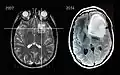

Imágenes por resonancia magnética de un paciente con astrocitoma, que muestran la progresión del tumor en el transcurso de siete años